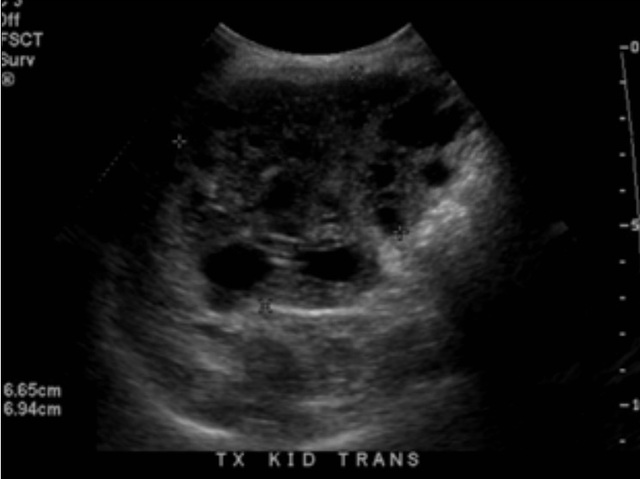

另一名肾脏移植接受者是一名 57 岁男性,伴有慢性间质性肾炎。在肾脏移植手术中未发现移植肾脏形态的异常,手术超声检查中发现在肾皮质和盂旁均发现类圆形囊肿,直接分别为 1.7cm 和 1.8cm。数年后肾脏检查结果如下。